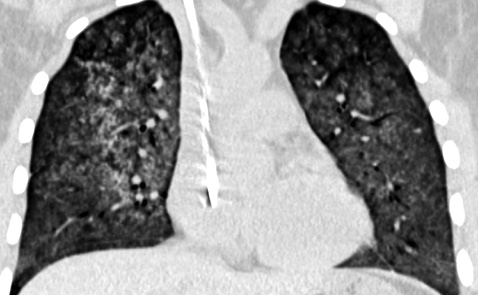

Пациенту было проведено комплексное обследование для уточнения диагноза. При ультразвуковом исследовании органов брюшной полости: размеры правой почки 127х54 мм; левой — 140х58 мм, паренхима толщиной в правой почке — 17 мм, в левой — 19 мм, дифференцированная, корковый слой диффузно повышенной эхогенности; небольшое количество свободной жидкости во фланках. Эхокардиография: без существенных изменений, ФВ — 60%. Клапанный аппарат без изменений, локальных нарушений сократимости, признаков легочной гипертензии и наличия свободной жидкости в полости перикарда не выявлено. Допплеровское исследование сосудов верхних и нижних конечностей — без диагностически значимых симп­томов. Мультиспиральная компьютерная томография (МСКТ) органов грудной клетки от 31.07. 2017 г. — на аксиальных и корональных КТ-срезах обоих легких субтотально, кроме самых крайних периферических отделов, определяется значительное снижение пневматизации легочной паренхимы по типу «матового стекла» и альвеолярного компонента (диффузное альвеолярное кровоизлияние). Проходимость трахеобронхиального дерева не нарушена (рис.1 а–г).

Рис. 1 а–г.

Данные МСКТ органов грудной клетки пациента К. от 31.07.2017 г. до начала иммуносупрессивной терапии. На аксиальных и корональных КТ-срезах обоих легких субтотально, кроме самых крайних периферических отделов, определяется значительное снижение пневматизации легочной паренхимы по типу «матового стекла» и альвеолярного компонента (диффузное альвеолярное кровоизлияние). Проходимость трахеобронхиального дерева не нарушена